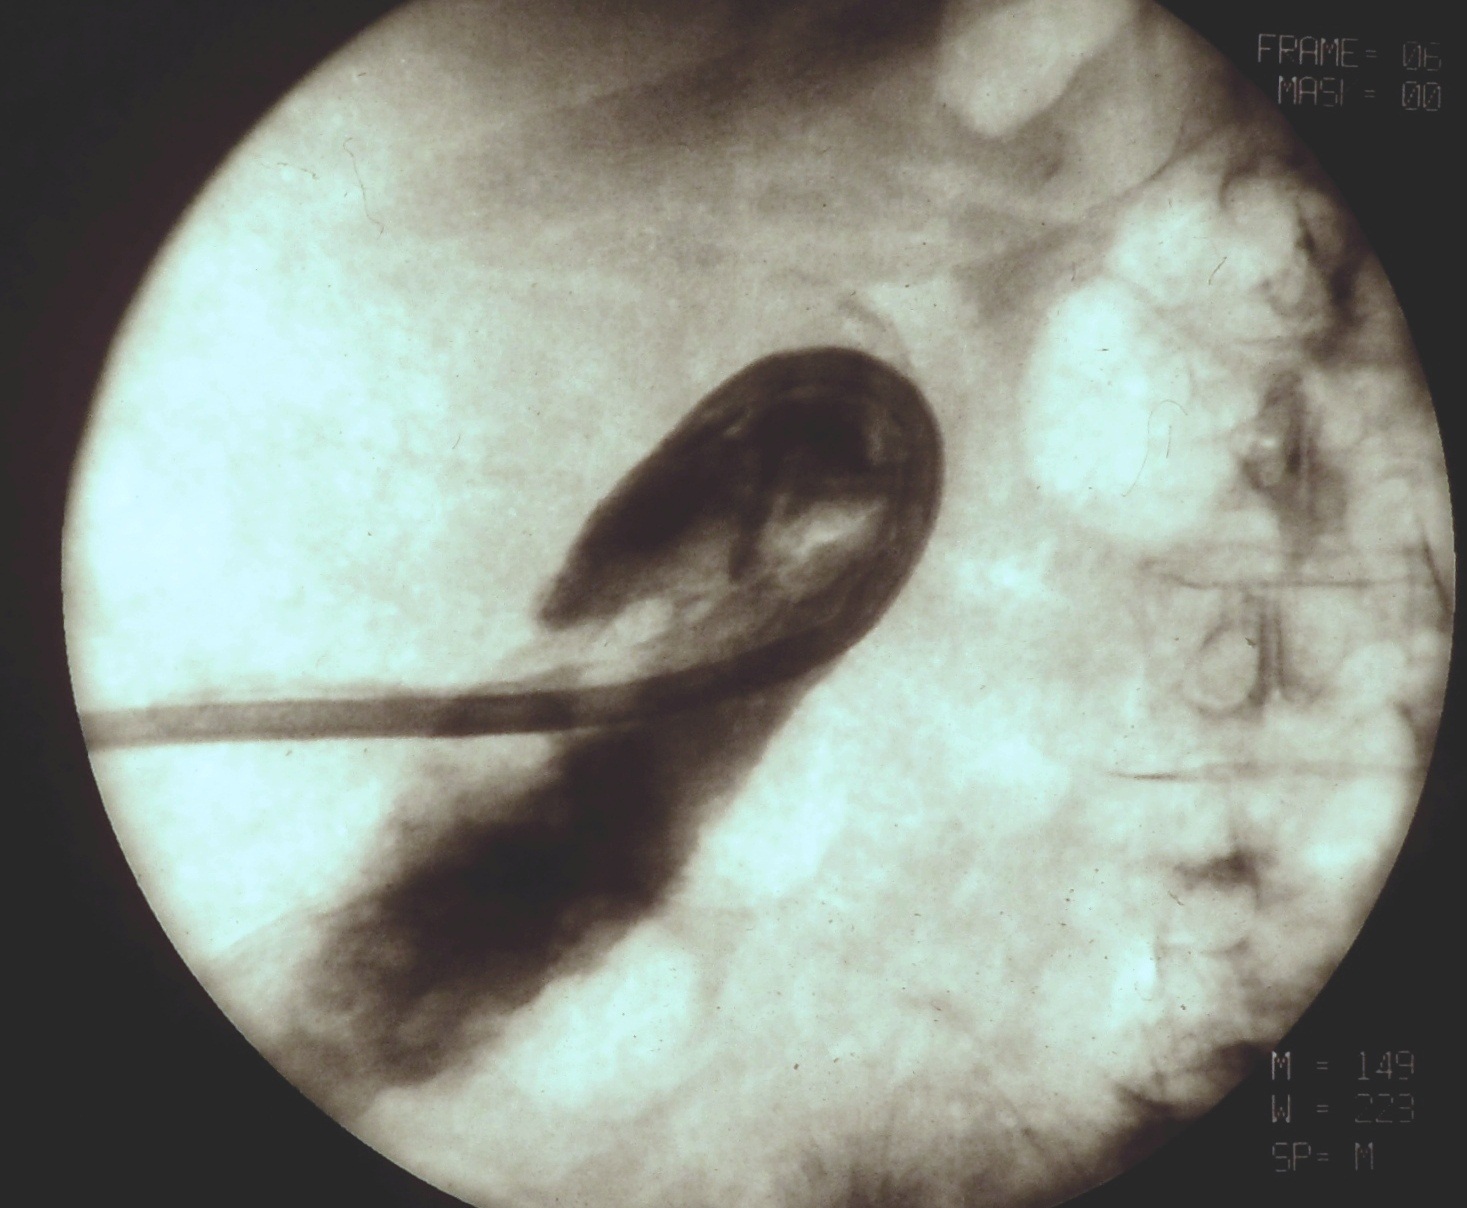

During this procedure X-ray or US is used to guide the insertion of a 22G (Chiba needle) from a right IX. or X. intercostals position into a dilated intrahepatic biliary branch. After the Chiba needle is well positioned the intra and extrahepatic biliary tree is filled with contrast material. (Figure 21.)

Image

Figure 21. – PTC (Percutaneous transhepatic cholangiography)